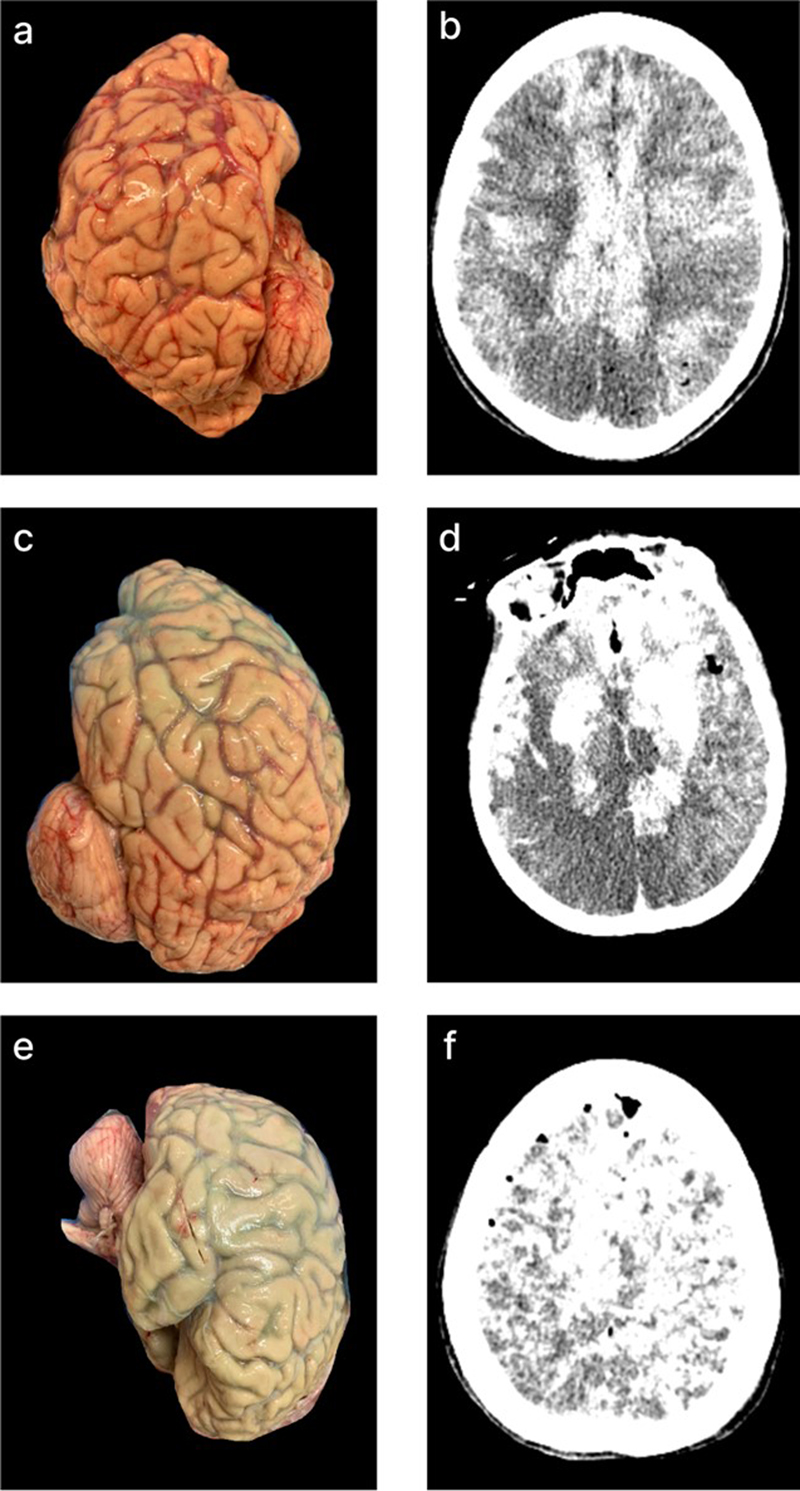

Quality of perfusion in gross images

We developed a semi-quantitative rating scale to measure the extent of tissue perfusion in areas corresponding to each of six major cerebral arteries (i.e. the left and right anterior cerebral artery, middle cerebral artery, and posterior cerebral artery), as well as both sides of the cerebellum. Perfusion quality was assessed based on degree of pallor, clearance of surface blood vessels, visible tissue stiffness, and the presence of colored dye when used at a concentration sufficient for visualization (Figure 2). For a subset of data, perfusion quality based on these images was graded separately by two independent raters. These grades had an ICC of 0.691 (95 % CI 0.542–0.799), indicating good interrater reliability. Qualitatively, we found that in nearly all cases, perfusion appeared patchy achieved across the surface of the brain – both between and within vascular territories, for reasons that remain unclear.

Figure 2.

Representative gross examination images showing perfusion rated to be each of the four grades (0, 1, 2, and 3) with in the vascular distributions of the anterior cerebral artery (ACA), middle cerebral artery (MCA), and posterior cerebral artery (PCA). For grade 0, we did not have a single brain with a grade of 0 in all three regions, so different brain samples were used for each representative image. Donor IDs: 169 (a), 183 (b, c), 205 (d, e, f), 197 (g, h, i), 126 (j, k, l).

The mean perfusion quality grades across both hemispheres were 1.94 ± 0.09 (standard error of the mean) for the ACA distribution, 1.75 ± 0.08 for the MCA, 1.75 ± 0.08 for the PCA, and 1.29 ± 0.08 for the cerebellum (Figure 3). There was no significant difference between the grades in the ACA and MCA distributions (t-test, p-value = 0.11). The grades in the ACA and MCA were each significantly higher than those in the PCA (t-test, p-values = 1.2e-5 and 0.003, respectively) and the cerebellum (t-test, p-values = 1.1e-7 and 7.7e-5, respectively). This indicates that perfusion quality was relatively higher in areas supplied by the anterior circulation (ACA and MCA) compared to those supplied by the posterior circulation (PCA and cerebellum). On the other hand, no consistent difference was found in perfusion quality between the left and right hemispheres, although some brains exhibited a slightly greater perfusion on one side than the other.